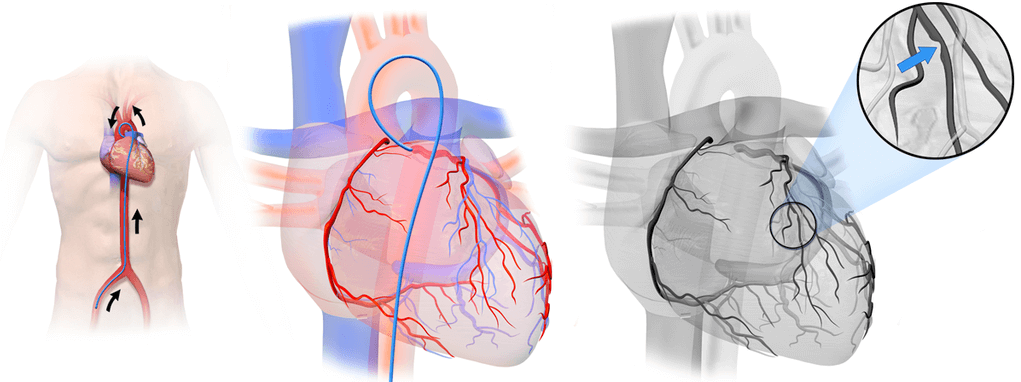

관상동맥은 심장에 혈액을 공급하는 혈관이므로 관상동맥에 문제가 생기면 심장수술을 해야 합니다. 그러나 피부를 통해 관상동맥에 접근하기 때문에 가슴을 여는 개심술(open heart surgery, 開心術)을 하지 않아도 된다는 장점이 있습니다. 상처 부위가 작아서 회복이 빠릅니다.

대퇴동맥(femoral artery) 또는 요골동맥(radial artery)을 통해 혈류에 접근한 후 관상동맥카테터를 사용하여 관상동맥에 풍선을 삽입해서 좁아진 관상동맥의 내경을 넓히고 관상동맥이 넓어진 상태를 유지할 수 있도록 스텐트를 삽입합니다.